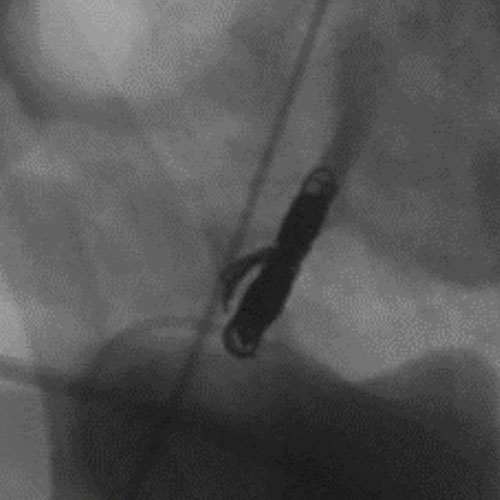

Embold Fibered Coil shown in left internal femoral artery Ruby Standard Coil shown in left internal femoral artery

Left internal femoral artery

5 Ruby Standard 6x20

Embold Fibered Coil shown in right internal femoral artery Embold Fibered Coil shown in right internal femoral artery

Right internal femoral artery

3 Embold Fibered Coil 6x20